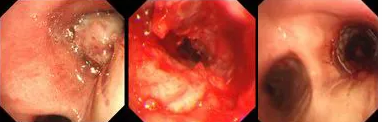

原來(lái),秦爺爺入院時(shí)診斷為“右主支氣管”鱗狀細(xì)胞癌伴壞死。他的右主支氣管被腫瘤完全堵塞,混合性狹窄。面罩吸氧10升/分的狀況下,指脈氧只有85%,無(wú)法平躺,呼吸困難,病情十分危急,隨時(shí)有生命危險(xiǎn)。

經(jīng)評(píng)估并與家屬溝通同意后,歐陽(yáng)海峰副院長(zhǎng)決定為患者實(shí)施TTS氣道支架手術(shù)。手術(shù)當(dāng)天,在麻醉手術(shù)中心的配合下,歐陽(yáng)海峰副院長(zhǎng)為患者在局麻下快速凍切腫瘤組織,實(shí)現(xiàn)右主支氣管再通,并經(jīng)氣管鏡活檢孔道迅速植入14*30 TTS支架一枚。支架植入過(guò)程耗時(shí)僅6秒,迅速緩解了患者的氣短瀕死癥狀。